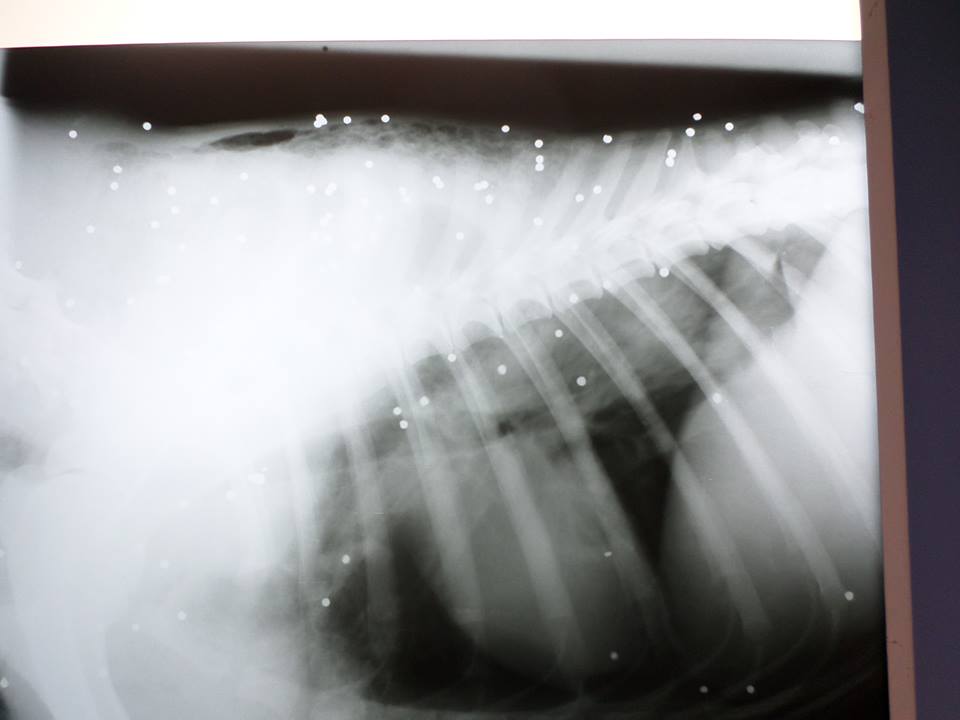

Το ζώο βγήκε από το κτηνιατρείο του Αντώνη Λυμπέρη χθες όπου νοσηλευόταν από τις 11 Μαΐου και μεταφέρθηκε στο σπίτι της Μαρίας Μωραΐτη η οποία δίνει τη δική της μάχη στην φροντίδα των αδέσποτων που υποφέρουν. Οι πληγές του Τζόρνταν από τα σκάγια έχουν ανοίξει και στις δύο πλευρές του σώματος του όπως εξήγησε στο www.zoosos.gr η Ερμιόνη Γιαννακού.

Οι φωτογραφίες με το ζώο να είναι ξαπλωμένο έξω από τα σπίτια στο Καρποχώρι είναι ενδεικτικό της αδιαφορίας των κατοίκων της περιοχής, καθώς σύμφωνα με τον κτηνίατρο το σκυλί είχε πυροβοληθεί τουλάχιστον επτά μέρες πριν το βρουν οι φιλόζωες γι’ αυτό και οι πληγές του είχαν σαπίσει.

Οι φωτογραφίες είναι αδιάψευστος μάρτυρας και αυτού του εγκλήματος!